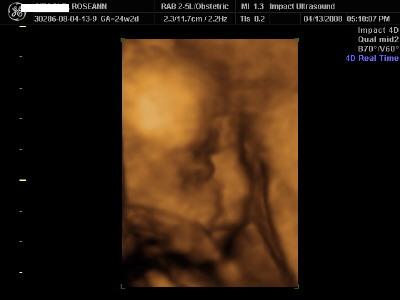

I just did the gold this past weekend and loved it

With tax, etc and the coupon, it came to 165 for the gold package.

I got a comfy bed and all the parents sat on couches and the sono was put up on a movie screen so everyone could see. My baby kept flipping but we were able to get him to cooperate and I got good pics. We got an 8 minute video, 6 3D pics printed out, and about 15 black and white 2D pics, plus a CD with about 20 3D pics. Both our families oved it Here are 2 of my pics - I was in my 25th week Image Attachment(s):